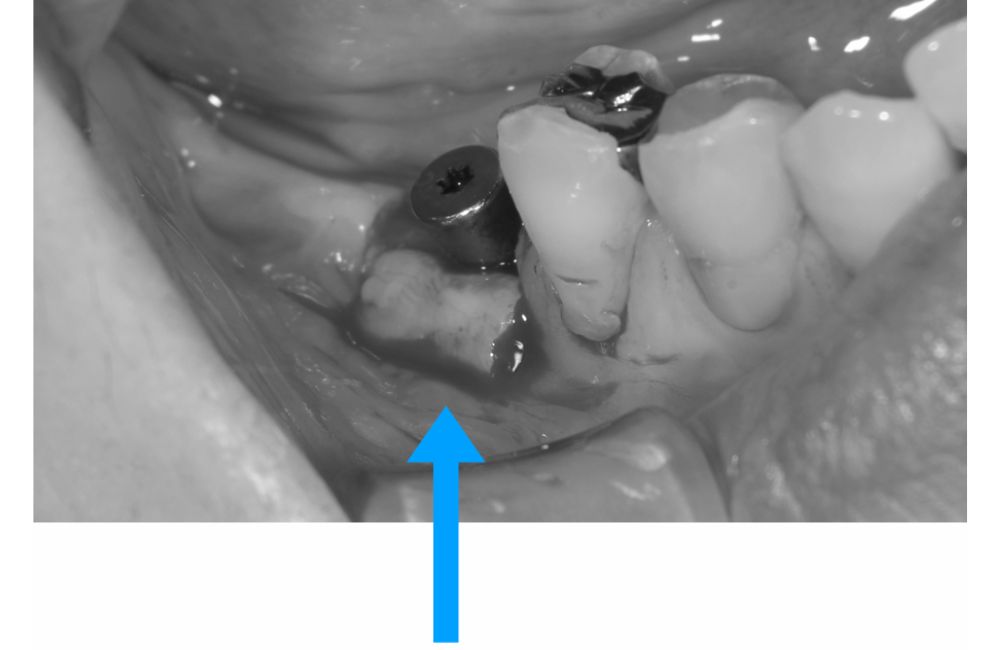

インプラント埋入

サージカルガイドを用いて適切な位置にインプラントを埋入することができました。

歯肉の治りも良好です。